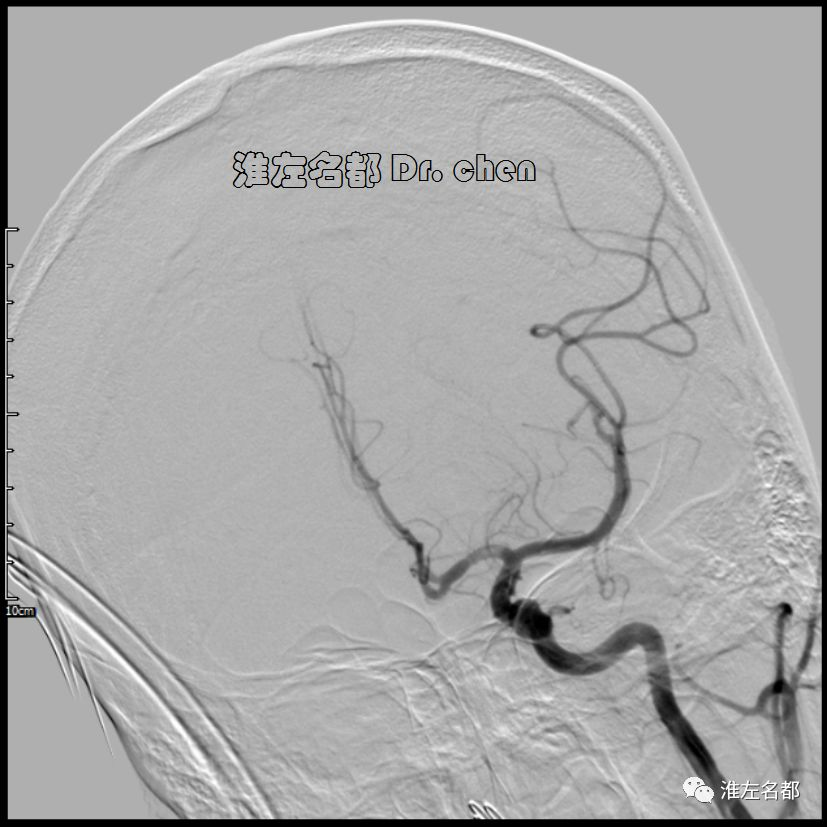

△经.035”泥鳅导丝将中间导管(Navien 058,125cm)送至左侧颈内动脉岩骨段,而后长鞘跟进至左侧颈内动脉,再经泥鳅导丝将中间导管送至海绵窦段,微导管(Rebar 27)在微导丝导引下进入左侧大脑中动脉M2段,造影证实位于真腔后,经微导管释放取栓支架(S AB 6*30mm)后造影:左侧颈内动脉远端充盈缺损,管腔严重狭窄;左侧大脑中动脉近端严重狭窄。

3.脑动脉夹层临床确诊依赖于影像学检测到典型夹层征象:内膜征/双腔征、长段不规则/丝线样狭窄、壁内血肿、夹层动脉瘤等。本患儿DSA显示左侧颈内动脉末端和大脑中动脉主干长段狭窄,且大脑中动脉主干狭窄呈“丝线样”,符合夹层影像学征象。

4.文献罕有报道颅内动脉夹层闭塞所致脑卒中急诊血管治疗案例,具体治疗策略也不明确。在本病例,应用S AB 6*30mm支架结合中间导管,以中间导管逆向回收的SWIM技术成功开通夹层所致的颅内前循环极重度狭窄。笔者使用上述技术是基于以下考虑: